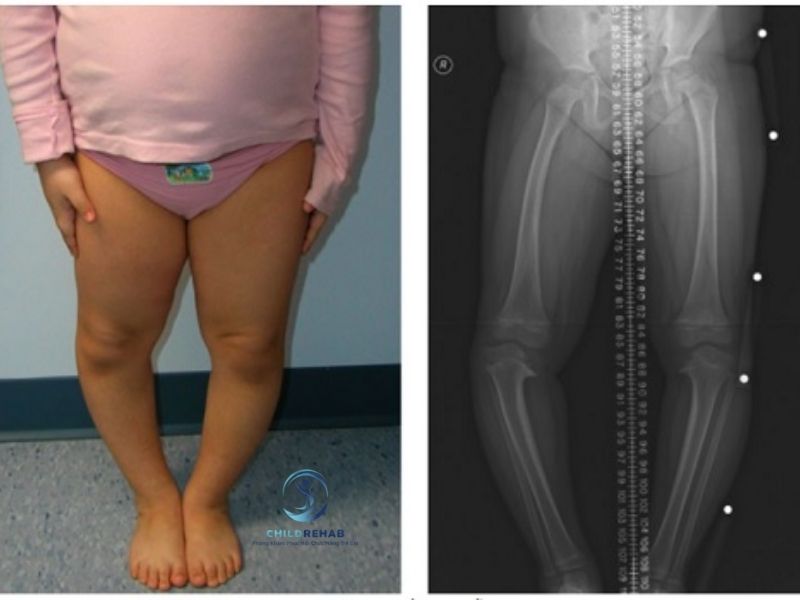

Trong quá trình phát triển vận động, không ít phụ huynh nhận thấy con mình có biểu hiện hai chân cong ra ngoài, thường được gọi là chân chữ O. Đây có thể là hiện tượng sinh lý bình thường ở một số giai đoạn phát triển, nhưng cũng có thể là dấu hiệu của những vấn đề cần được theo dõi và can thiệp kịp thời. Chính vì vậy, việc tìm hiểu về chân chữ O ở trẻ là bước quan trọng giúp cha mẹ có cái nhìn đúng và đầy đủ hơn về tình trạng này.

Một trong những câu hỏi phổ biến là quá trình đánh giá chân chữ O ở trẻ thường gồm những gì, và khi nào thì nên đưa trẻ đi kiểm tra chuyên sâu. Trên thực tế, việc đánh giá không chỉ đơn giản là quan sát hình dạng chân mà còn bao gồm nhiều yếu tố liên quan như tư thế, vận động, cấu trúc xương và sự phát triển tổng thể của trẻ. Nếu chỉ dựa vào cảm quan bên ngoài, cha mẹ có thể dễ dàng bỏ sót những dấu hiệu quan trọng hoặc ngược lại, lo lắng quá mức khi chưa cần thiết.

Việc đánh giá đúng giúp phân biệt giữa chân chữ O sinh lý (có thể tự điều chỉnh theo thời gian) và chân chữ O bệnh lý (cần can thiệp). Đây là yếu tố quyết định hướng theo dõi và hỗ trợ tiếp theo. Đồng thời, đánh giá sớm còn giúp hạn chế những ảnh hưởng lâu dài đến dáng đi, khả năng vận động và sự phát triển thể chất của trẻ.